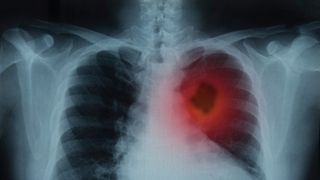

„Plămânii arătau extrem de rău, era o pneumonie extinsă bilaterală cu acumulări în alveole, practic foarte puțin din plămâni mai era, restul era compromis. Pacienta practic nu mai avea suprafață pulmonară cu care să respire. Manifestările acestei boli sunt neașteptate. Aici nu prea văd o soluție în cazul acesta, că s-ar fi putut face ceva.

De obicei formele astea grave cam așa se întâmplă, pacienta este relativ bine și dintr-o dată se prăbușește. Așa s-a întâmplat și în cazul ăsta”, a declarat la Digi24 Dan Crainic, director medical al Spitalului de Urgență Alba Iulia.